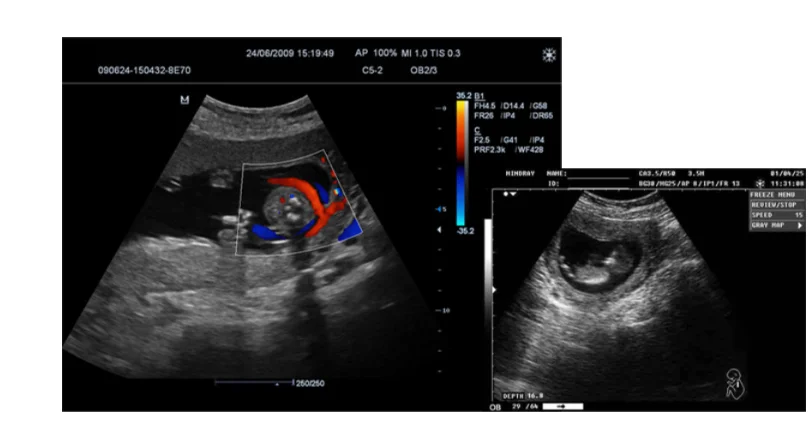

For Compatible GE: Logiq 7 Logiq9 Logiq A5 Logiq P5 Logiq S6 Vivid 7 Expert Vivid 7 Pro Convex Array Abdominal Probe 4C